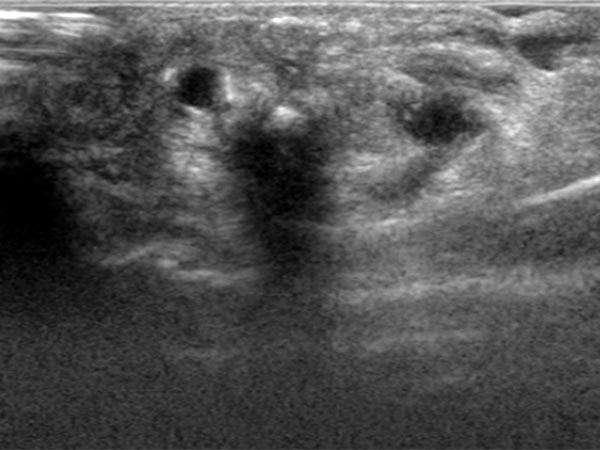

Im Ultraschall imponiert subkutan epifaszial am dritten Finger eine dilatierte Drainagevene aus der digitalen AVM. In der Farbduplexsonographie (FKDS) bestätigt sich der fast-flow arterio-venöse Shunt mit hohem Durchfluss.

Nachdem es technisch nicht möglich ist, die AVM zur Re-Embolisation nur von transarteriell zu behandeln, wird sonographisch gesteuert nun der perkutane Behandlungsweg in Direktpunktionstechnik gewählt.

Perkutanes, sonograhisch gesteuertes Vorschieben der Punktionsnadel in die Drainagevene der digitalen AVM.